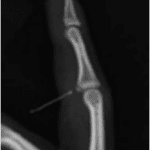

Suggest X-ray

Finger dislocation treatment management is really simple. Generally the hand therapist at Action Rehab Hand Therapy Clinic will read your xrays and understand the mechanism of your dislocation. Treatment will consist of a small dorsal finger splint for a period of up to 6 weeks.

Fig 1: Basic Treatment

A metal splint being used to treat a finger dislocation. It does not allow a full range of motion.